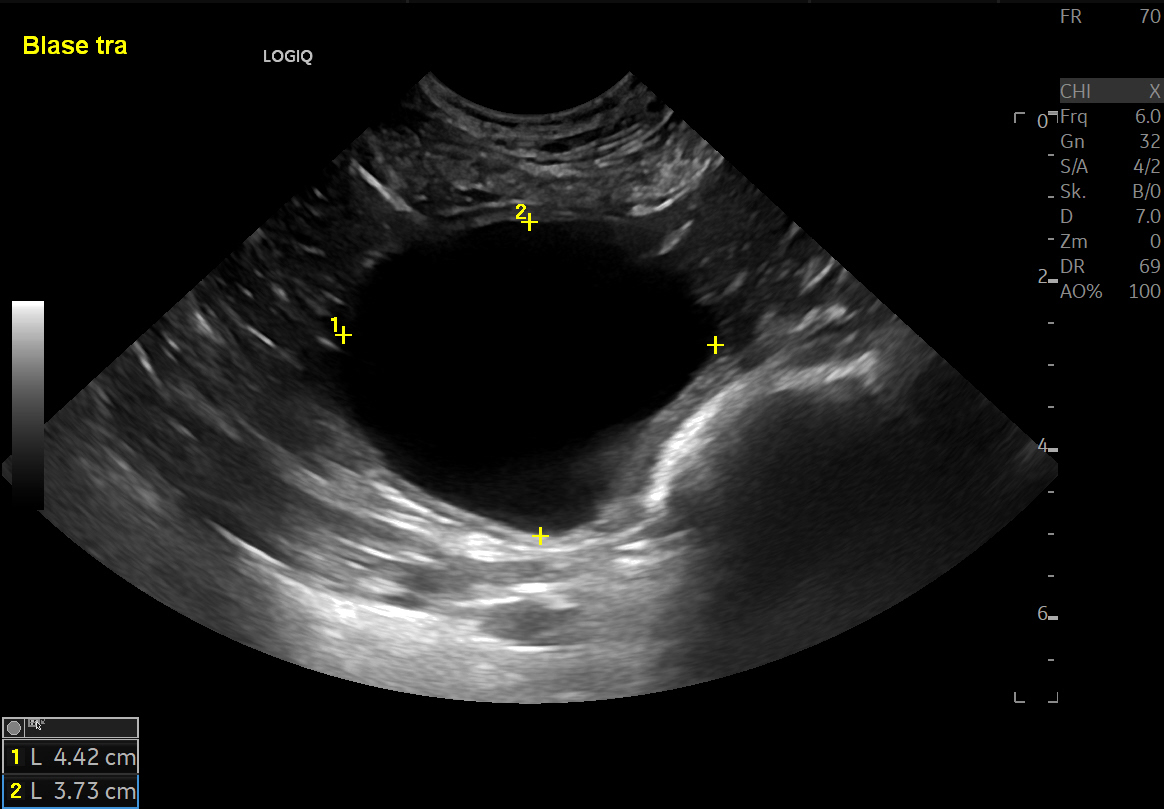

Vom American College of Veterinary Internal Medicine wurden Konsensus-Richtlinien zur Harninkontinenz des Hundes aufgelegt. Der vorliegende Fortbildungsartikel nimmt diese Richtlinien zum Anlass, den aktuellen Wissensstand über die Harninkontinenz des Hundes praxisgerecht zusammenzufassen. Bei der Harninkontinenz handelt es sich um einen weder zu Ort noch Zeit passenden ungewollten Urinverlust. Alle Altersklassen und alle Rassen können mit unterschiedlichem Schweregrad betroffen sein. Ein ausführliches Anamnesegespräch soll dabei helfen, eine Einteilung in Harnspeicherstörungen und Harnentleerungsstörungen vorzunehmen. Die Anamnese beinhaltet Fragen zum Allgemeinzustand, zum Trinkverhalten, zum Harnabsatz selbst und zum Harnträufeln. Bei der klinischen Untersuchung geht es um den Allgemeinzustand und einen orientierenden neurologischen Status. Die innere Untersuchung erfolgt mittels rektaler Untersuchung von Harnröhre und Prostata sowie mittels Ultraschall, Röntgen, Kontrast-Röntgen und CT. Labordiagnostisch werden Harnstatus und ein Blut-Profil erhoben. Vor einer invasiven Diagnostik mittels Urethrozystoskopie kann eine diagnostische medikamentöse Therapie begonnen werden. Zu den häufigsten Harnspeicherstörungen gehören eine kastrationsbedingte Sphinkterschwäche, eine Ureter-Ektopie und eine Instabilität des M. detrusor vesicae. Bei Harnspeicherstörungen ist vorab eine Polyurie/Polydipsie auszuschließen beziehungsweise aufzuarbeiten. Harnentleerungsstörungen unterteilt man in mechanische und funktionelle Entleerungsstörungen. Funktionell häufig ist die idiopathische Detrusor-Sphinkter-Dyssynergie mittelgroßer bis großer Rüden. Neurologische Erkrankungen können sowohl Harnspeicherstörungen als auch funktionelle Harnentleerungsstörungen verursachen. In vielen Fällen stehen bei Harninkontinenz wirksame Medikamente zur Verfügung, in anderen Fällen sind endoskopische oder offen chirurgische Korrektureingriffe etabliert. Hilfsweise besteht die Option zur Einlage eines präpubischen Dauerkatheters.

The American College of Veterinary Internal Medicine presented initial consensus guidelines for canine urinary incontinence this year. This review article lead this author to summarize the current knowledge of urinary incontinence in the dog in a practical manner. Urinary incontinence is defined as involuntary loss of urine that is neither appropriate to the place nor the time of voiding. All age groups and all breeds of dogs can be affected with varying degrees of severity. The amount of urine loss does not correlate with owners’ motivation to seek veterinary care. A detailed history should help differentiate urinary storage disorders from urinary voiding disorders. The history includes questions about the general health condition, drinking behaviour, micturition behaviour and dribbling of urine. Clinical examination should cover the general condition of the dog, neurological status, external examination of the urogenital tract and rectal examination of the urethra and prostate. Diagnostic imaging, namely ultrasound, radiography (survey and contrast radiography) and CT are indicated for further examination. Laboratory diagnostics include urinary status and a hematological and biochemical profile. Before proceeding with invasive urethrocystoscopy, diagnostic drug therapy can be started. The most common urinary storage disorders include urethral sphincter mechanism incompetence, ectopic ureter, and detrusor instability. In the case of urinary storage disorders, polyuria/polydypsia should be ruled out or worked on at first presentation. Urinary voiding disorders are subdivided into mechanical and functional disorders. Idiopathic detrusor urethral dyssynergia represents a common functional disorder in medium to large size male dogs. Neurological disorders can cause both urinary storage and functional voiding disorders. In many cases, effective medication is available; in other cases, therapeutic endoscopic or open surgical procedures have been established. Placement of a percutaneous cystostomy cathete may be a final option.